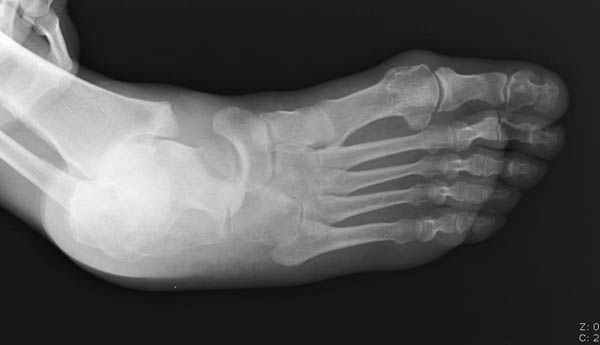

Уважаемые участники русского Ортофорума, поздравляю всех со всеми прошедшими праздниками: Новым годом, Рождеством, Hanukkah, Kwanzaa, желаю участникам всего наилучшего и здоровья.Повреждение таранной кости.Больной 81г автоавария, повреждение таранной кости, здесь снимки.

Вдогонку по поводу перелома таранной кости, больная 81, не страдает диабетом, перелом закрытый, в первый же день поступления ограничились временным наружным фиксатором (как на снимке).

За пару недель насчитал 5 больных с переломом таранной кости, из них двое с двусторонним повреждением.

Из-за отека на стопе тактика лечения у всех была

одинаковая: временная наружная фиксация до спадения отека, при изолированных переломах они выписывались домой и через дней 7 госпитализировались на оперативное лечение.

Примеры на снимке...